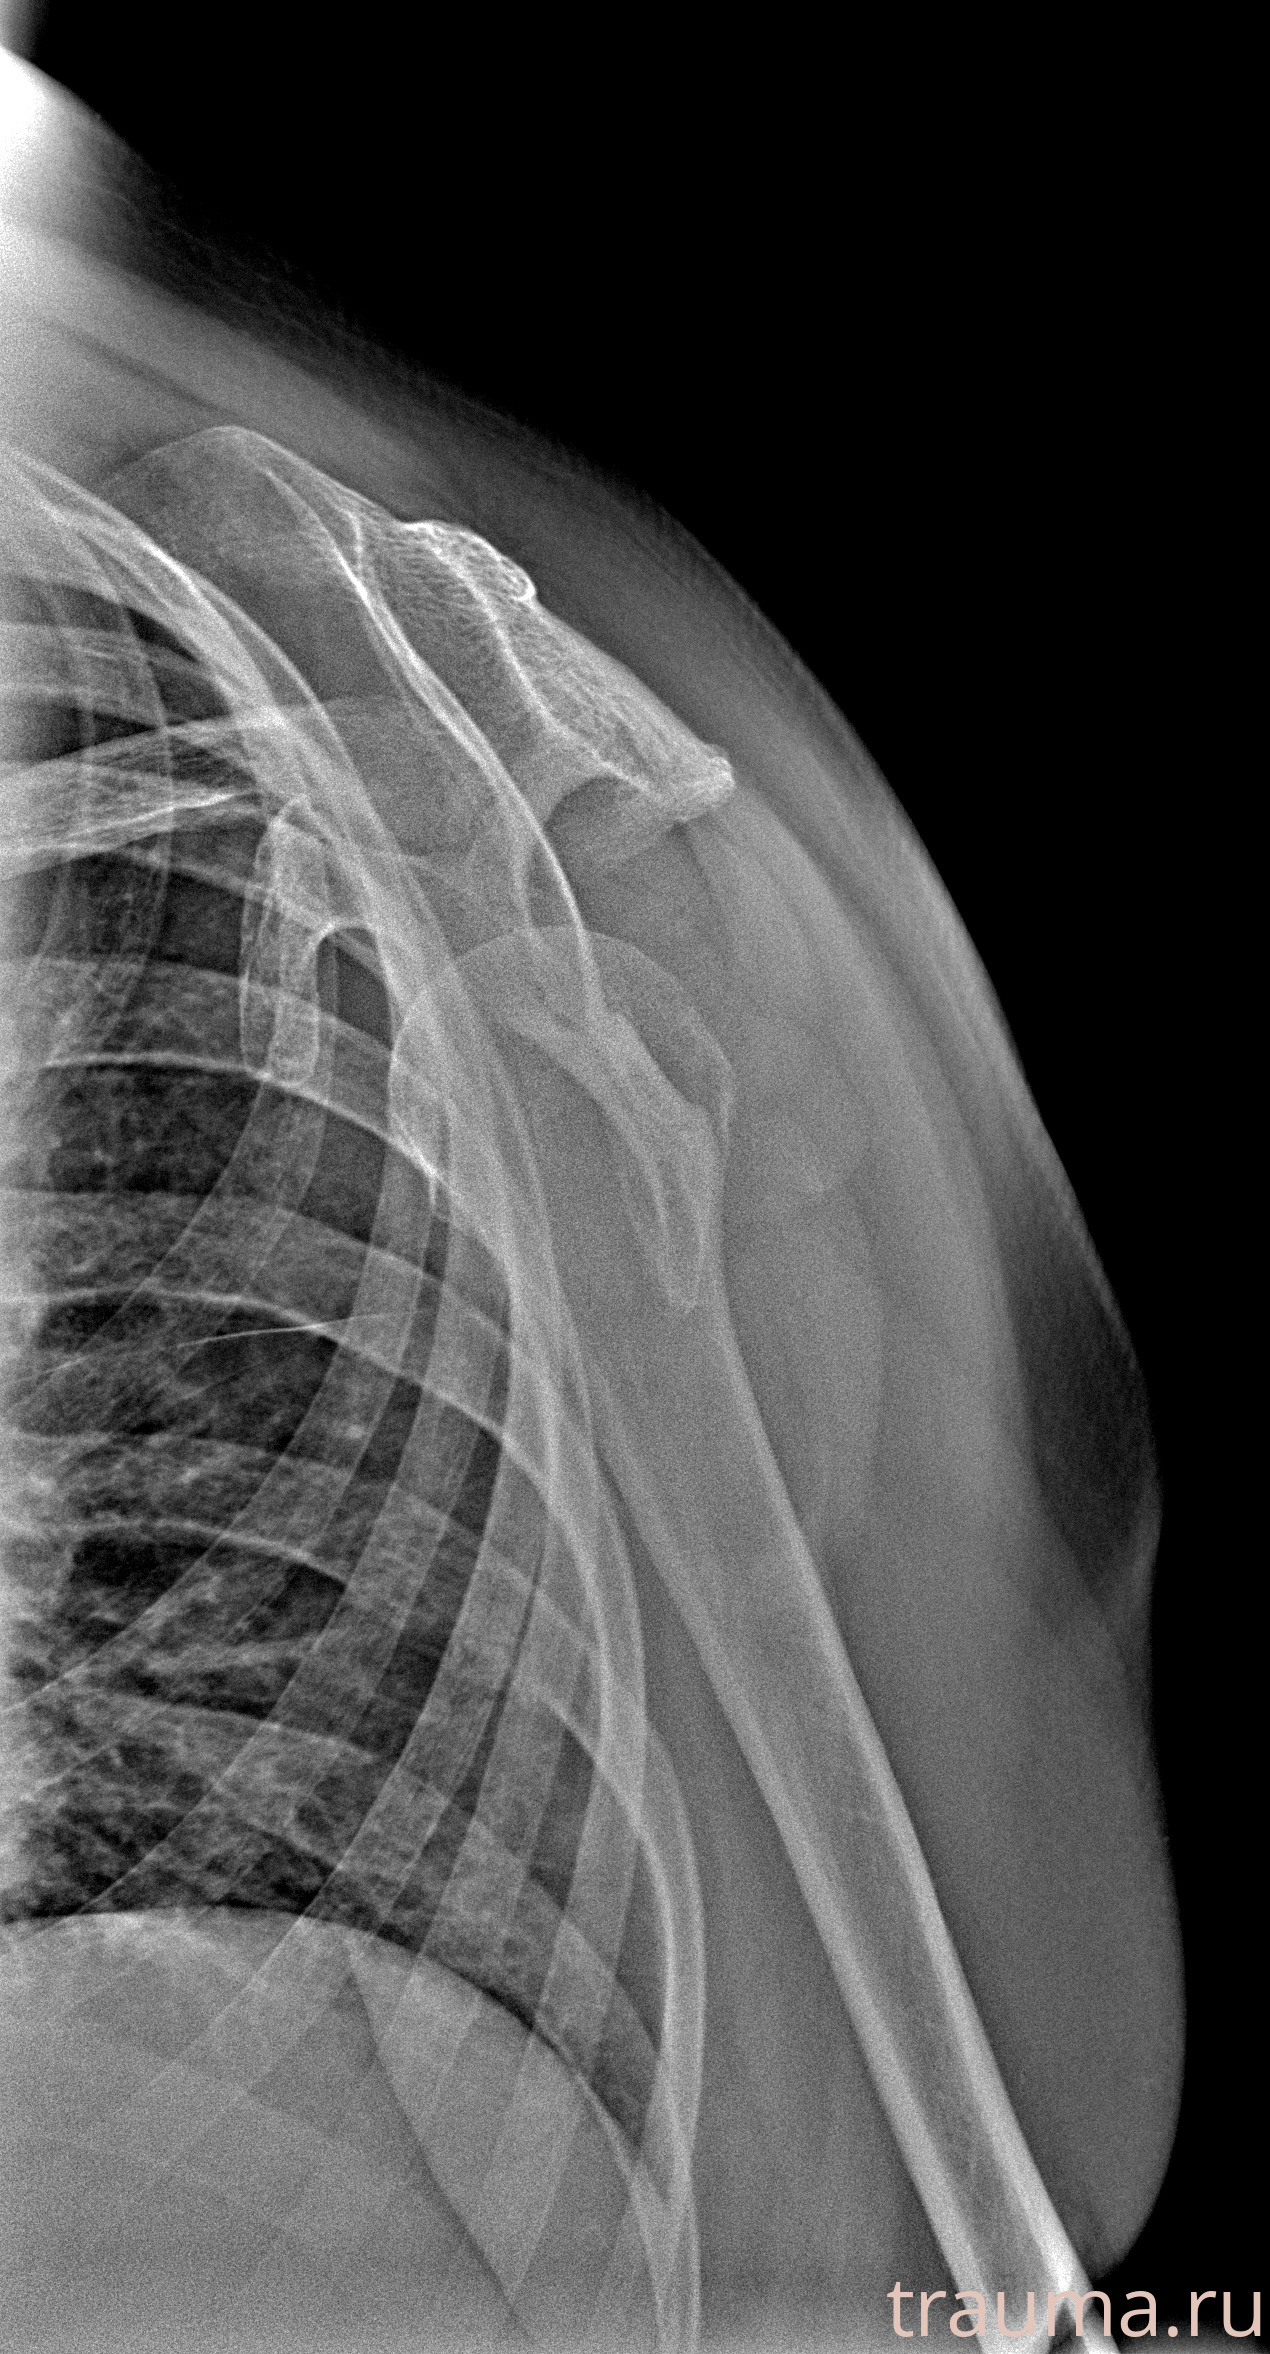

Рентгенограммы

Рентген на дому: по вашему адресу приезжает врач-рентгенолог, травматолог-ортопед с мобильным рентгеновским аппаратом, проводит диагностику травмы или заболевания, делает необходимые рентгенограммы, дает рекомендации по дальнейшему лечению. Получить качественные снимки в домашних условиях возможно благодаря уникальной методике, разработанной МосРентген Центром для института  Склифосовского